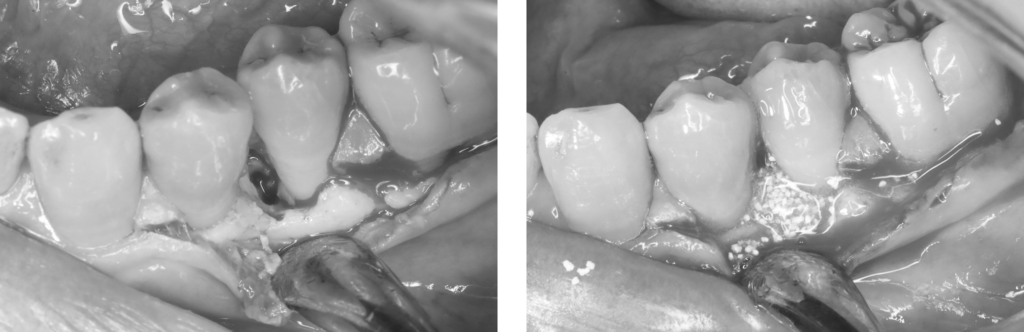

外科後2年です。

骨様組織で骨(歯槽骨)が溶けていた部分が満たされていることが確認できます。

治療前後です。

外科後2年の歯肉の状態です。

歯肉が下がっておらず、良好な状態です。